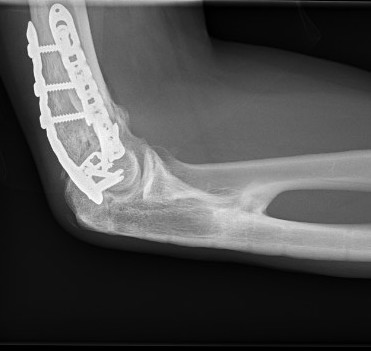

Elbow HOElbow HO Excision Post op

+/- hinged external fixator

Elbow Post HO Excision